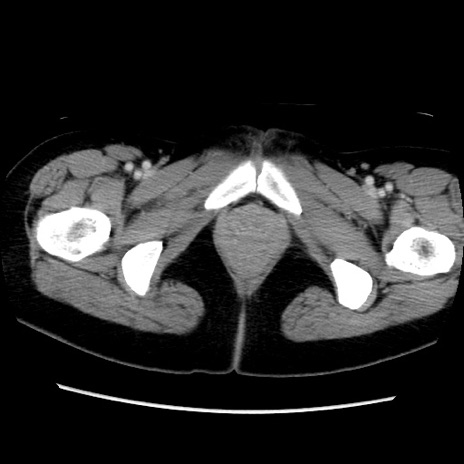

症例39(横断像)

【症例】40歳代女性

【主訴】上下腹部痛

【現病歴】2日目から下腹部痛あり。夜間は痛みで眠れなかった。昨日より上腹部痛と下痢が出現。臥位で痛みは軽快したため、休んでいた。本日になって臥位でも立位でも痛みが強くなってきたため救急要請。

【既往歴】子宮内膜症

【身体所見】部:平坦・軟、左上下腹部に圧痛あり、反跳痛あり。

【データ】WBC 21800、CRP 26.78